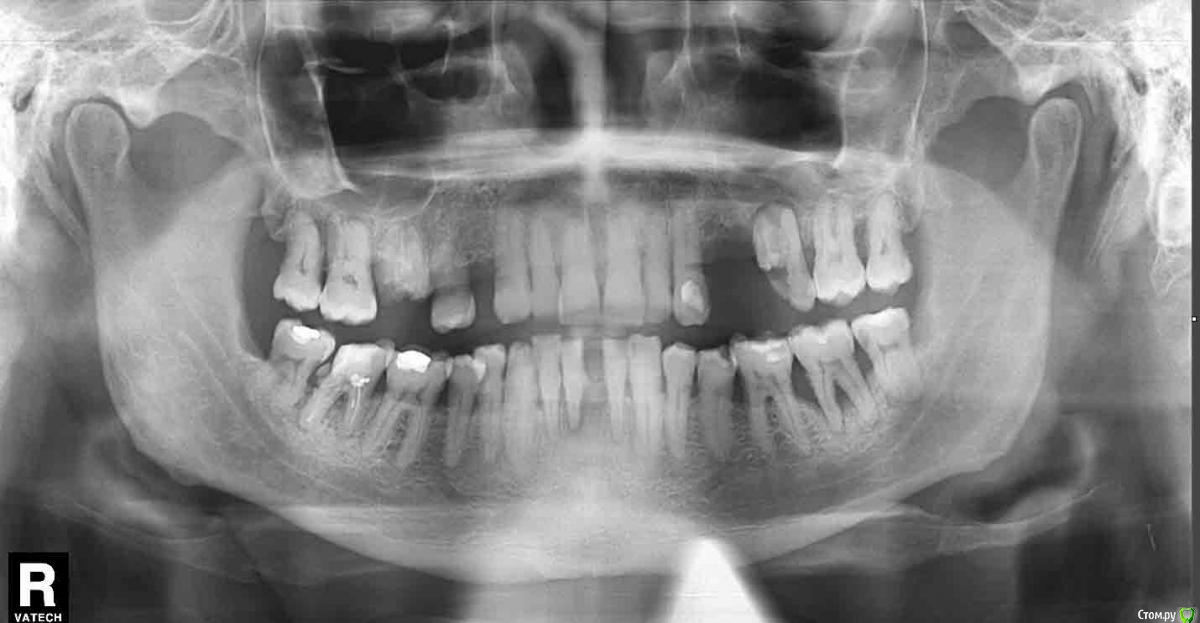

bobrdobr Опубликовано 14 ноября, 2016 Поделиться Опубликовано 14 ноября, 2016 Здравствуйте, У родственника непростая ситуация с зубами Рассматриваем различные варианты протезирования. Подскажите, можно ли где-то применить мосты или съемные протезы? Хотя бы как вариант на несколько лет. Понятно, что в идеале необходимо ставить импланты. Спасибо Ссылка на комментарий

bobrdobr Опубликовано 15 ноября, 2016 Автор Поделиться Опубликовано 15 ноября, 2016 (изменено) все возможно..Нужна какая-то дополнительная информация? Конкретный вопрос по нижним резцам. Предлагают 3 вариантаУдалить 41 и сделать съемный акриловый протез на 2 зуба Удалить все 3 оставшхся резца и сделать съемный акриловый протез на 4 зуба Удалить все 3 оставшхся резца и сделать мост с опорой на клыки Поставить "пластинку" у пародонтолога (на 1-2 года)Нравится вариант 1, хотя ортопед советует 2 - более стабильная фиксация. Как сделать выбор? По материалу стоит рассматривать нейлон или еще что-то или акрил подойдет? Изменено 15 ноября, 2016 пользователем bobrdobr Ссылка на комментарий

IvanK Опубликовано 17 ноября, 2016 Поделиться Опубликовано 17 ноября, 2016 Ну а как же пресловутое "второе мнение"? За этим большинство и идут на форум.для объективного второго мнения нужен очный осмотр в Вашем случае советовать что-то , не решая проблему боковых зубов, сложно если не смотреть на другие зубы, что не правильно, я бы удалил 41, оценил 32,42, рассмотрел вариант мостовидной конструкции ( возможно с вовлечением двоек) , это если не думать об имплантации.. Ссылка на комментарий

bobrdobr Опубликовано 17 ноября, 2016 Автор Поделиться Опубликовано 17 ноября, 2016 для объективного второго мнения нужен очный осмотр в Вашем случае советовать что-то , не решая проблему боковых зубов, сложно если не смотреть на другие зубы, что не правильно, я бы удалил 41, оценил 32,42, рассмотрел вариант мостовидной конструкции ( возможно с вовлечением двоек) , это если не думать об имплантации..Спасибо за развернутый ответ. Про осмотр понял. "Второе мнение" будем искать у себя в городе. Правильно понимаю, что с боковыми нужно разобраться, чтобы не жевать передними и не разрушать протезирование, которое на них будет сделано? Про мост понял. В каком случае мост на 32 и 42 может быть адекватным выбором?Предположу, что если запротезированы жевательные зубы, остановлен пародонтит, указанные резцы неподвижны и в хорошем состоянии. Каковы недостатки съемного протеза на два зуба 31,41? Ссылка на комментарий

IvanK Опубликовано 18 ноября, 2016 Поделиться Опубликовано 18 ноября, 2016 32 и 42 может быть адекватным выбором? нет, нужно включить и клыки Каковы недостатки съемного протеза на два зуба 31,41? главный недостаток - съемное 2 Ссылка на комментарий